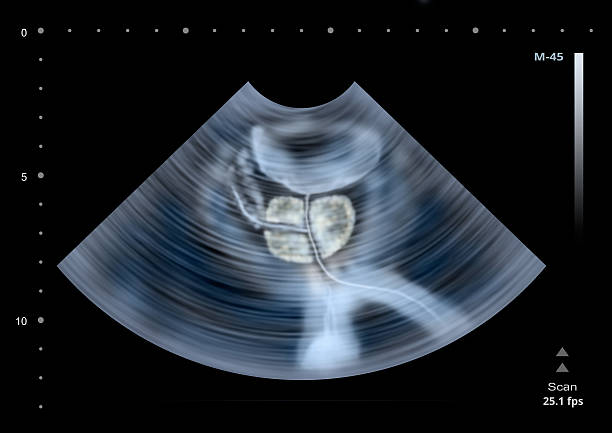

전립선암은 남성에서 가장 흔한 악성 종양 중 하나로, 전립선에서 발생하는 암입니다. 전립선은 남성의 생식기관 중 하나로, 회음부와 방광 사이에 위치하며, 요도 주위를 둘러싸고 있습니다. 전립선은 대부분의 경우 선천적으로 발생한 것은 아니며, 남성이 노화에 따라 서서히 성장하면서 발생하는 것으로 알려져 있습니다.